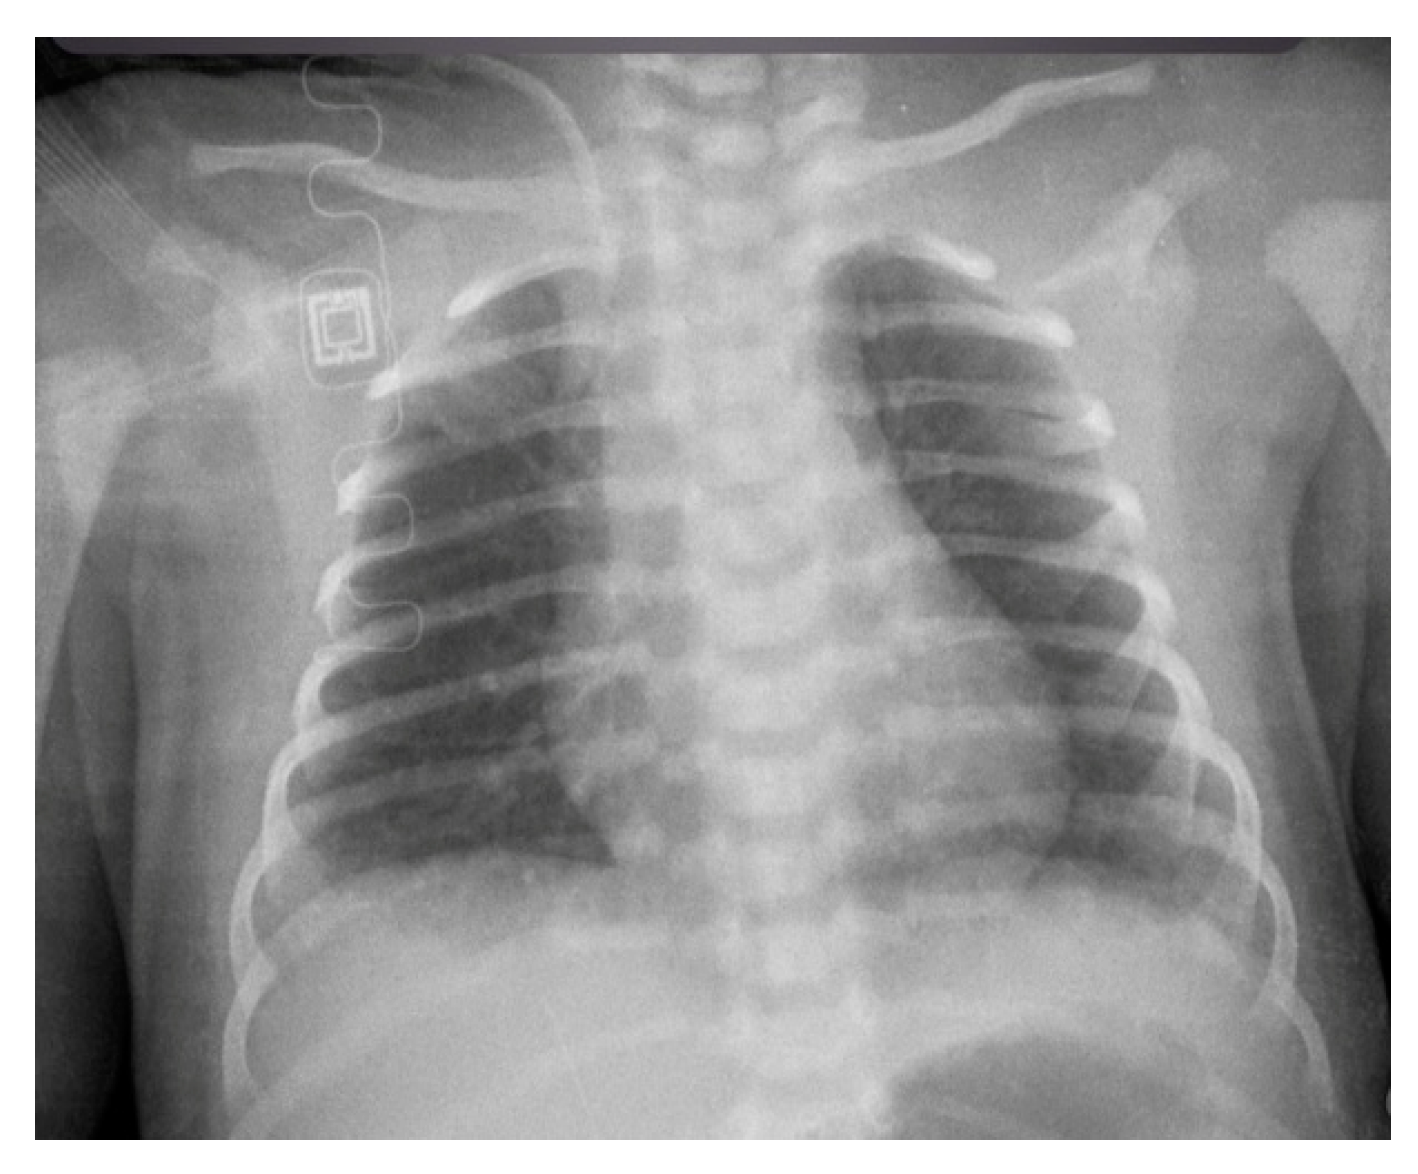

Conventional Radiology Evaluation of Neonatal Intravascular Devices (NIVDs): A Case Series

3. Results